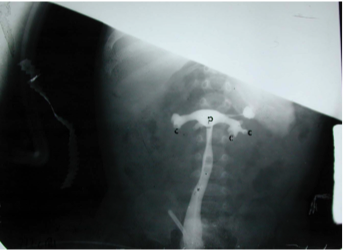

What is that?

Double Collecting duct system in a single kidney